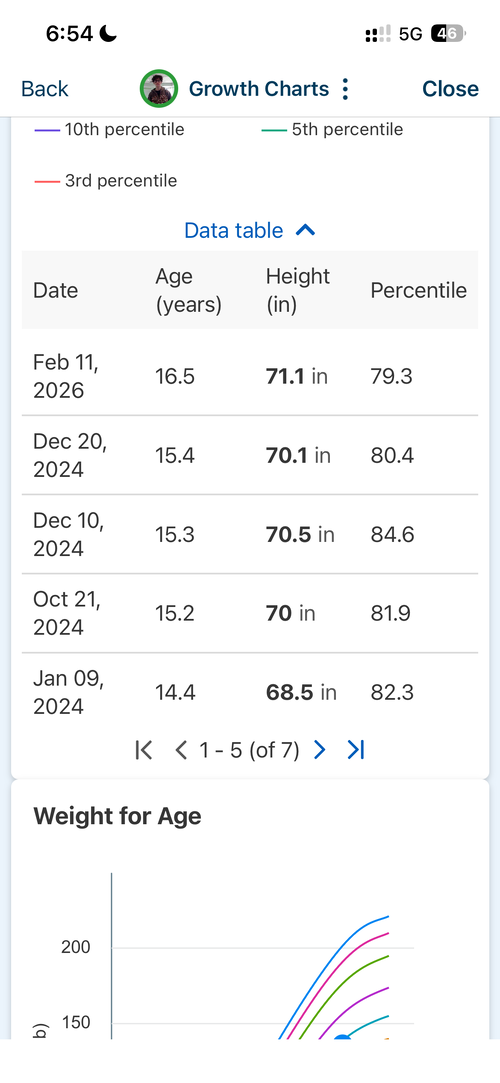

16.6 yr old male at 5'11.1" in height currently. Father is 6'1.5" and Mother is 5'8". I have images of my growth chart along with an X-Ray of my wrist attached. I also attached recent bloodwork tests of TESTOSTERONE, IGF-1 and Cortisol.